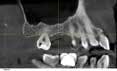

Case 1: Osteotome sinus lift with simultaneous implant placement

A 53-year-old female with a medical history of hypothyroidism, seasonal allergies, and asthma taking Synthroid and Singula presented to my office with pain in No. 3, failed root canal therapy, and a fracture. The tooth was deemed hopeless and extraction and implant placement was treatment planned. Under local anesthesia, tooth No. 3 was sectioned into three pieces and extracted. The sockets were debrided, filled with gel foam, and closed with chromic gut sutures. Healing was uneventful. The patient did not return for two years for follow-up. A CT scan was taken, which confirmed that approximately5 mm of bone remained below the floor of the sinus. After reviewing the options with the patient, a treatment plan of an internal sinus lift (osteotome), bone graft, platelet-rich fibrin (PRF) and simultaneous implant placement was agreed upon. Under local anesthesia, a full thickness flap with two vertical releasing incisions was performed at tooth No. 3 site. A trephine bur was used to a depth of 4 mm. An osteotome was then employed to infracture the bone core, which remained attached to the Schneiderman membrane. A bone graft consisting of DFDBA, anorganic bovine bone, and PRF was used in the osteotomy to increase the vertical bone height using sequential osteotomes. After sufficient elevation, a 7x9 tapered implant was placed on low speed to 50% of the implant depth. The remaining placement of implant was done with a hand torque on 50 ncm to allow for further expansion of the alveolar housing. A healing abutment was placed using the principles of platform switching. Healing was uneventful, and integration was successful.